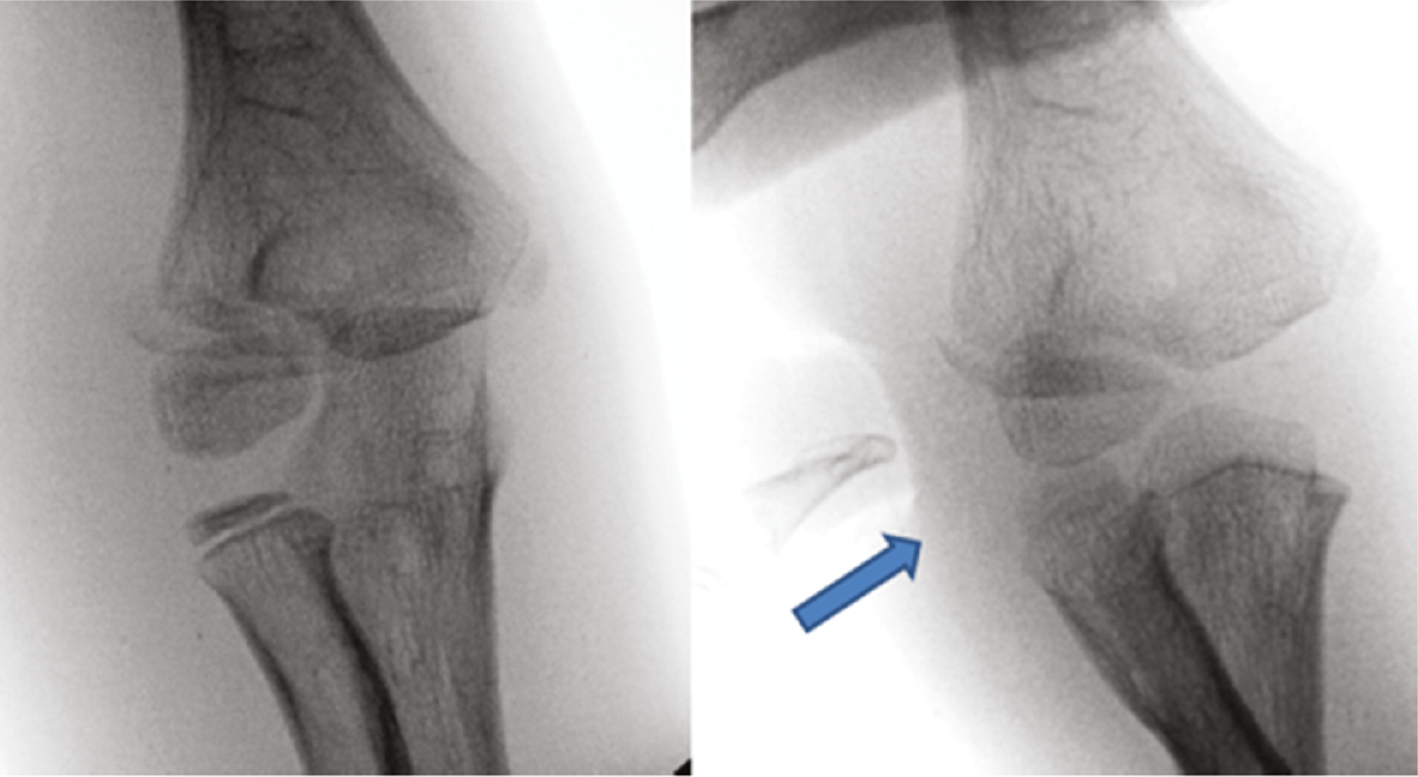

Radiographs should include an AP, lateral, and internal rotation oblique of the distal humerus are recommended to evaluate the injury. Often the internal oblique will show the greatest degree of displacement which will ultimately guide treatment.2 Ordering an AP, lateral, and internal oblique x-ray of the elbow will not fully characterize the displacement, as these radiographs are not orthogonal to the distal humerus.

Jakob and Song have both described classification systems that can guide treatment.1,3 In minimally displaced fracture (<2 mm), closed treatment with a long arm cast and close observation is appropriate. For fractures with 2-4 mm of displacement, an attempt at closed reduction, percutaneous pinning, and arthrogram to assess articular congruity are recommended. Fractures with greater than 4 mm of displacement typically require open reduction and pinning, and articular alignment is assessed through direct visualization or via arthrogram. Additionally, an open fracture would be an indication for open reduction and pinning to allow for appropriate irrigation and debridement of the injury. Lastly, a nonunion would also require an open approach and internal fixation.